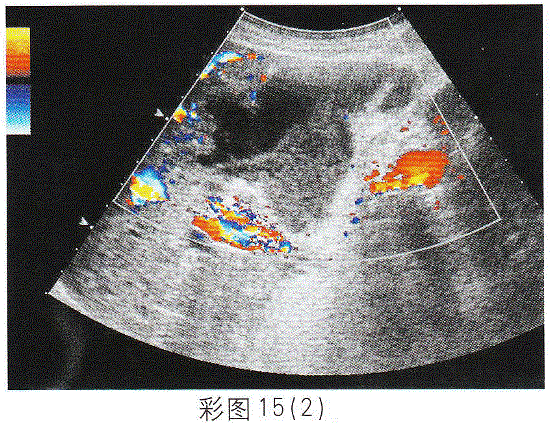

问题 临床资料:男,82岁,自述右上腹疼痛伴高热5天,持续性加重。 临床物理检查:右上腹压痛明显,肌紧张,莫菲氏征阳性。 化验检查:白细胞16.27×10/L,中性粒细胞0.939%。 超声综合描述:胆囊形态失常,内透声不清亮,前壁连续不完整(箭头所示),前壁外可见极低一无回声区,形态不规则,CDFI:囊壁可见动脉血流信号,V28.9cm/s,超声莫菲氏征阳性。见下图及彩图15。 {图3} {图4} {图5} 超声提示:

选项 A.胆囊泥沙样结石(充满型) B.胆囊癌 C.急性胆囊炎胆囊穿孔 D.胆汁淤积

答案 C